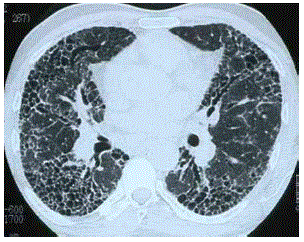

Dilatação da via aérea distal, com bronquiolectasias e bronquiolomucoceles, é a tradução de um padrão identifcado pela alta resolução no tórax.

Baseado na imagem disponibilizada, qual o seu diagnóstico?

Cistos pulmonares podem ter diversas formas de apresentação, além de poderem aparecer de forma isolada ou um conjunto.